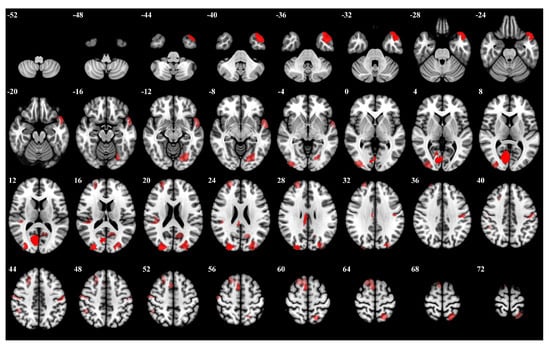

3.1. Importance Weight Characteristics of Brain Regions

| Rank | Brain Regions | Side | Centroid Coordinates (R A S) | Importance Weight |

|---|---|---|---|---|

| 1 | Visual 19 | R | 9 −74 9 | 0.315 |

| 2 | Visual 26 | R | 27 −87 21 | 0.314 |

| 3 | Limbic Temporal Pole 6 | L | −40 −21 −27 | 0.274 |

| 4 | Visual 27 | L | −12 −71 20 | 0.272 |

| 5 | Somatomotor 17 | L | −51 −7 43 | 0.271 |

| 6 | Frontoparietal Control Cingulate 1 | R | 6 −26 28 | 0.253 |

| 7 | Salience Ventromedial Attention Medial 4 | R | 12 −34 43 | 0.247 |

| 8 | Visual 5 | L | −23 −73 −10 | 0.238 |

| 9 | Visual 18 | R | 35 −89 2 | 0.238 |

| 10 | Dorsal Attention Posterior 16 | L | −20 −57 66 | 0.234 |

| 11 | Somatomotor 21 | R | 52 −13 49 | 0.231 |

| 12 | Somatomotor 10 | R | 41 −29 18 | 0.228 |

| 13 | Frontoparietal Control Lateral Prefrontal Cortex 8 | R | 48 18 23 | 0.228 |

| 14 | Default Temporal 5 | L | −53 6 −11 | 0.226 |

| 15 | Default Precuneus Posterior Cingulate Cortex 2 | L | −13 −61 19 | 0.225 |

| 16 | Default Dorsal Prefrontal cortex an Medial Prefrontal Cortex 13 | R | 12 20 63 | 0.217 |

| 17 | Visual 28 | L | −32 −84 27 | 0.216 |

| 18 | Frontoparietal Control Parietal 5 | R | 54 −33 51 | 0.204 |

| 19 | Somatomotor 3 | R | 53 −14 6 | 0.203 |

| 20 | Default Dorsal Prefrontal cortex and Medial Prefrontal Cortex 12 | R | 12 −55 15 | 0.203 |